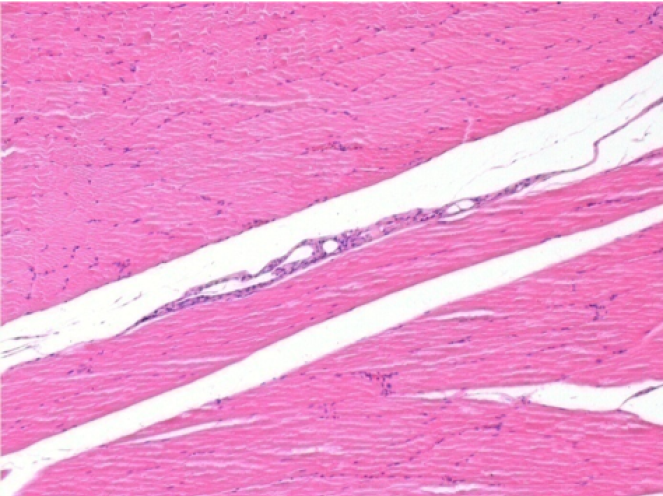

Через 10 днів після ін'єкції Ендопіл 0,1 мл в правий претибіальний м'яз.

Тут можна побачити утворення вакуолей, які оточені лімфоцитами. Вакуолі відрізняються від некрозу тканини. Присутність лімфоцитів пов'язана з проникністю клітинних мембран.